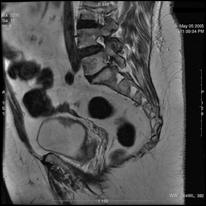

b). Neoplasm de col uterin, invaziv in vezica urinara

a. b.

a) Tumora de col uterin, invaziva in vezica urinara - pacienta s-a prezentat in anurie; b) Tumora de col uterin, operata (histerectomie totala + iradiere), recidivata, invadand vezica urinara si rectul - pacienta s-a prezentat cu hematurie